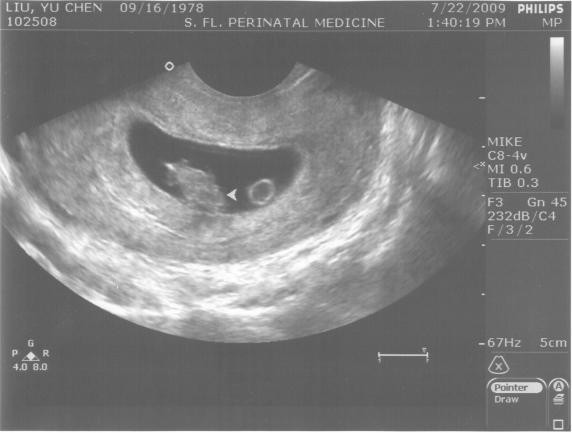

看看今日的小黑點生長情形

:

箭頭處的是baby~~旁邊有個圓圓的就是寳寳的的營養來源它會有一條cord連接到寳寳而它也是會讓媽媽噁心想兔的主要因素醫生說如果你有morning sickness 那就怪這個小圓圓吧~)。

小黑點年齡:

81天(好妙唷~1天也能說得出來)